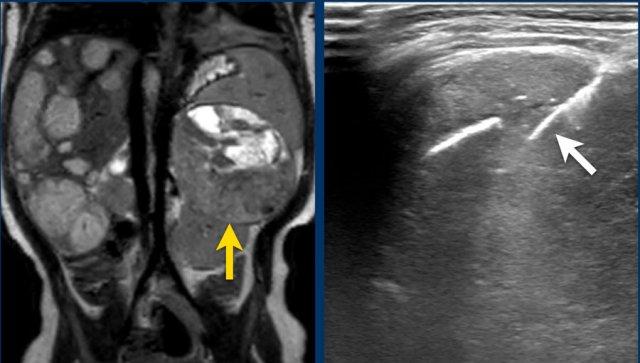

Hình ảnh

U nguyên bào thận ở thận trái của bé trai ba tuổi. Phần còn lại của thận trải dài trên khối u (dấu hiệu “móng vuốt” mũi tên). Khối u khá đồng nhất với một số vùng nang.

A. The tumor enhances less than the peripheral remnant of normal renal tissue (blue arrow). The left renal vein is open (yellow arrow). Solid parts of the tumor show diffusion restriction (white arrow)

Left sided nephroblastoma in a two-year-old girl. Note the para-aortal lymph node metastasis (arrow).